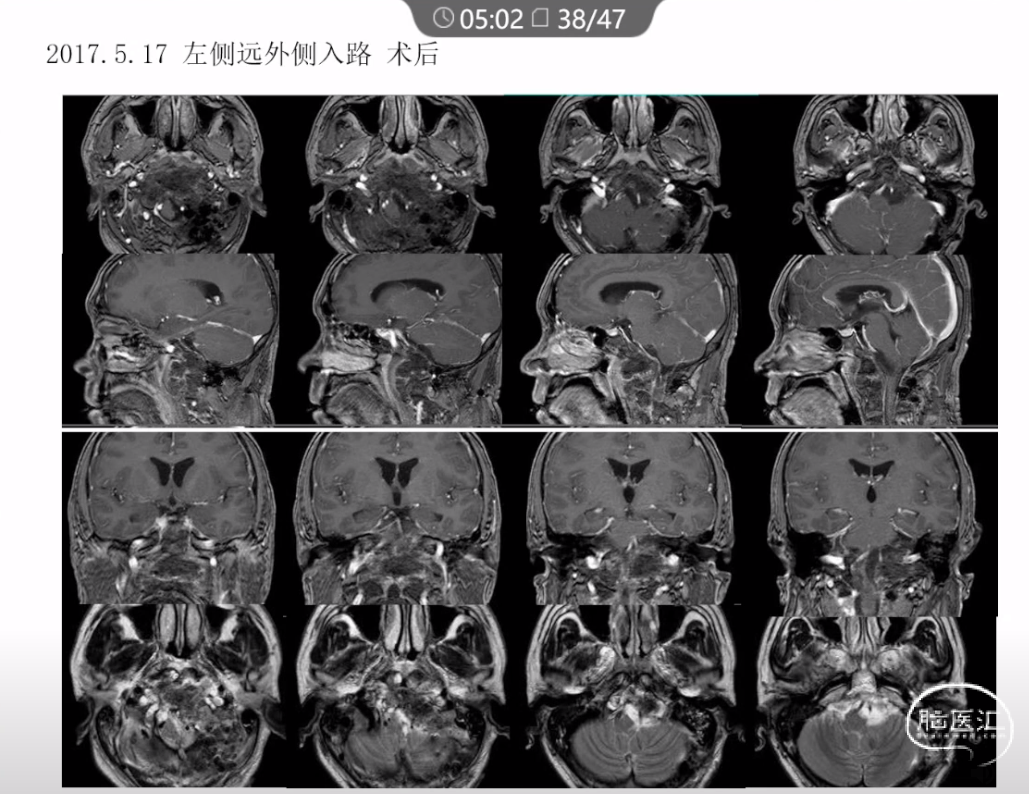

本文主要内容为:脊索瘤临床特点、治疗选择,以及多个手术病例。